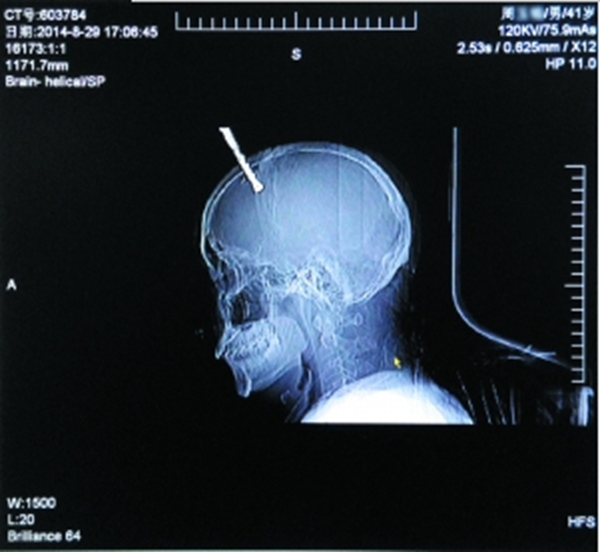

回首走过的2014,不禁发现,温暖就在身边,感动也时常陪伴。这里有历经半个世纪念念不忘的“保肾”之恩,有英勇施救花甲坠楼老人的蜘蛛侠医生,有古稀老人撰千字文追忆的温暖,有“换血少女”勇闯6小时的“鬼门关”脱...